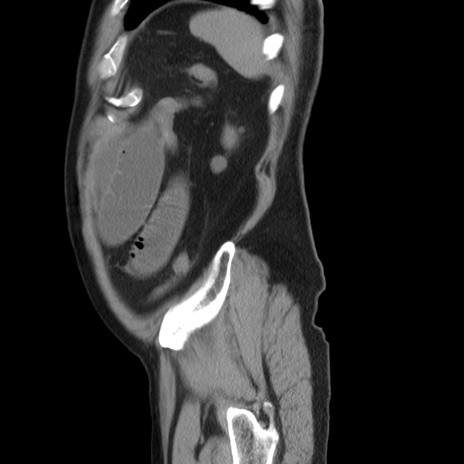

症例20(矢状断像)

【症例】 60歳代男性

【主訴】 腹部膨満、嘔吐

【現病歴】5日前頃より倦怠感を認め食事量減少し4日前の朝嘔吐、食事摂取困難となった。 3日前近医受診し点滴施行され整腸剤などを処方された。 当日他院を受診し、腹部膨満著明、炎症反応の上昇(CRP10.8、WBC11200)あり、紹介受診となる。

【身体所見】 意識JCS1 受け答えがはっきりしないBP 111/57mHg、 P 67bpm、、BT35.2°C、SpO2 97%(RA)、 腹部:膨隆、打診で鼓音あり、全体的に圧痛有り、腸蠕動音(-)、反跳痛ははっきりせず。

【データ】WBC 11400、CRP 14.20